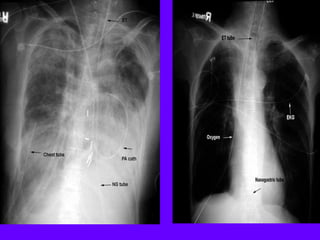

Chest Tubes